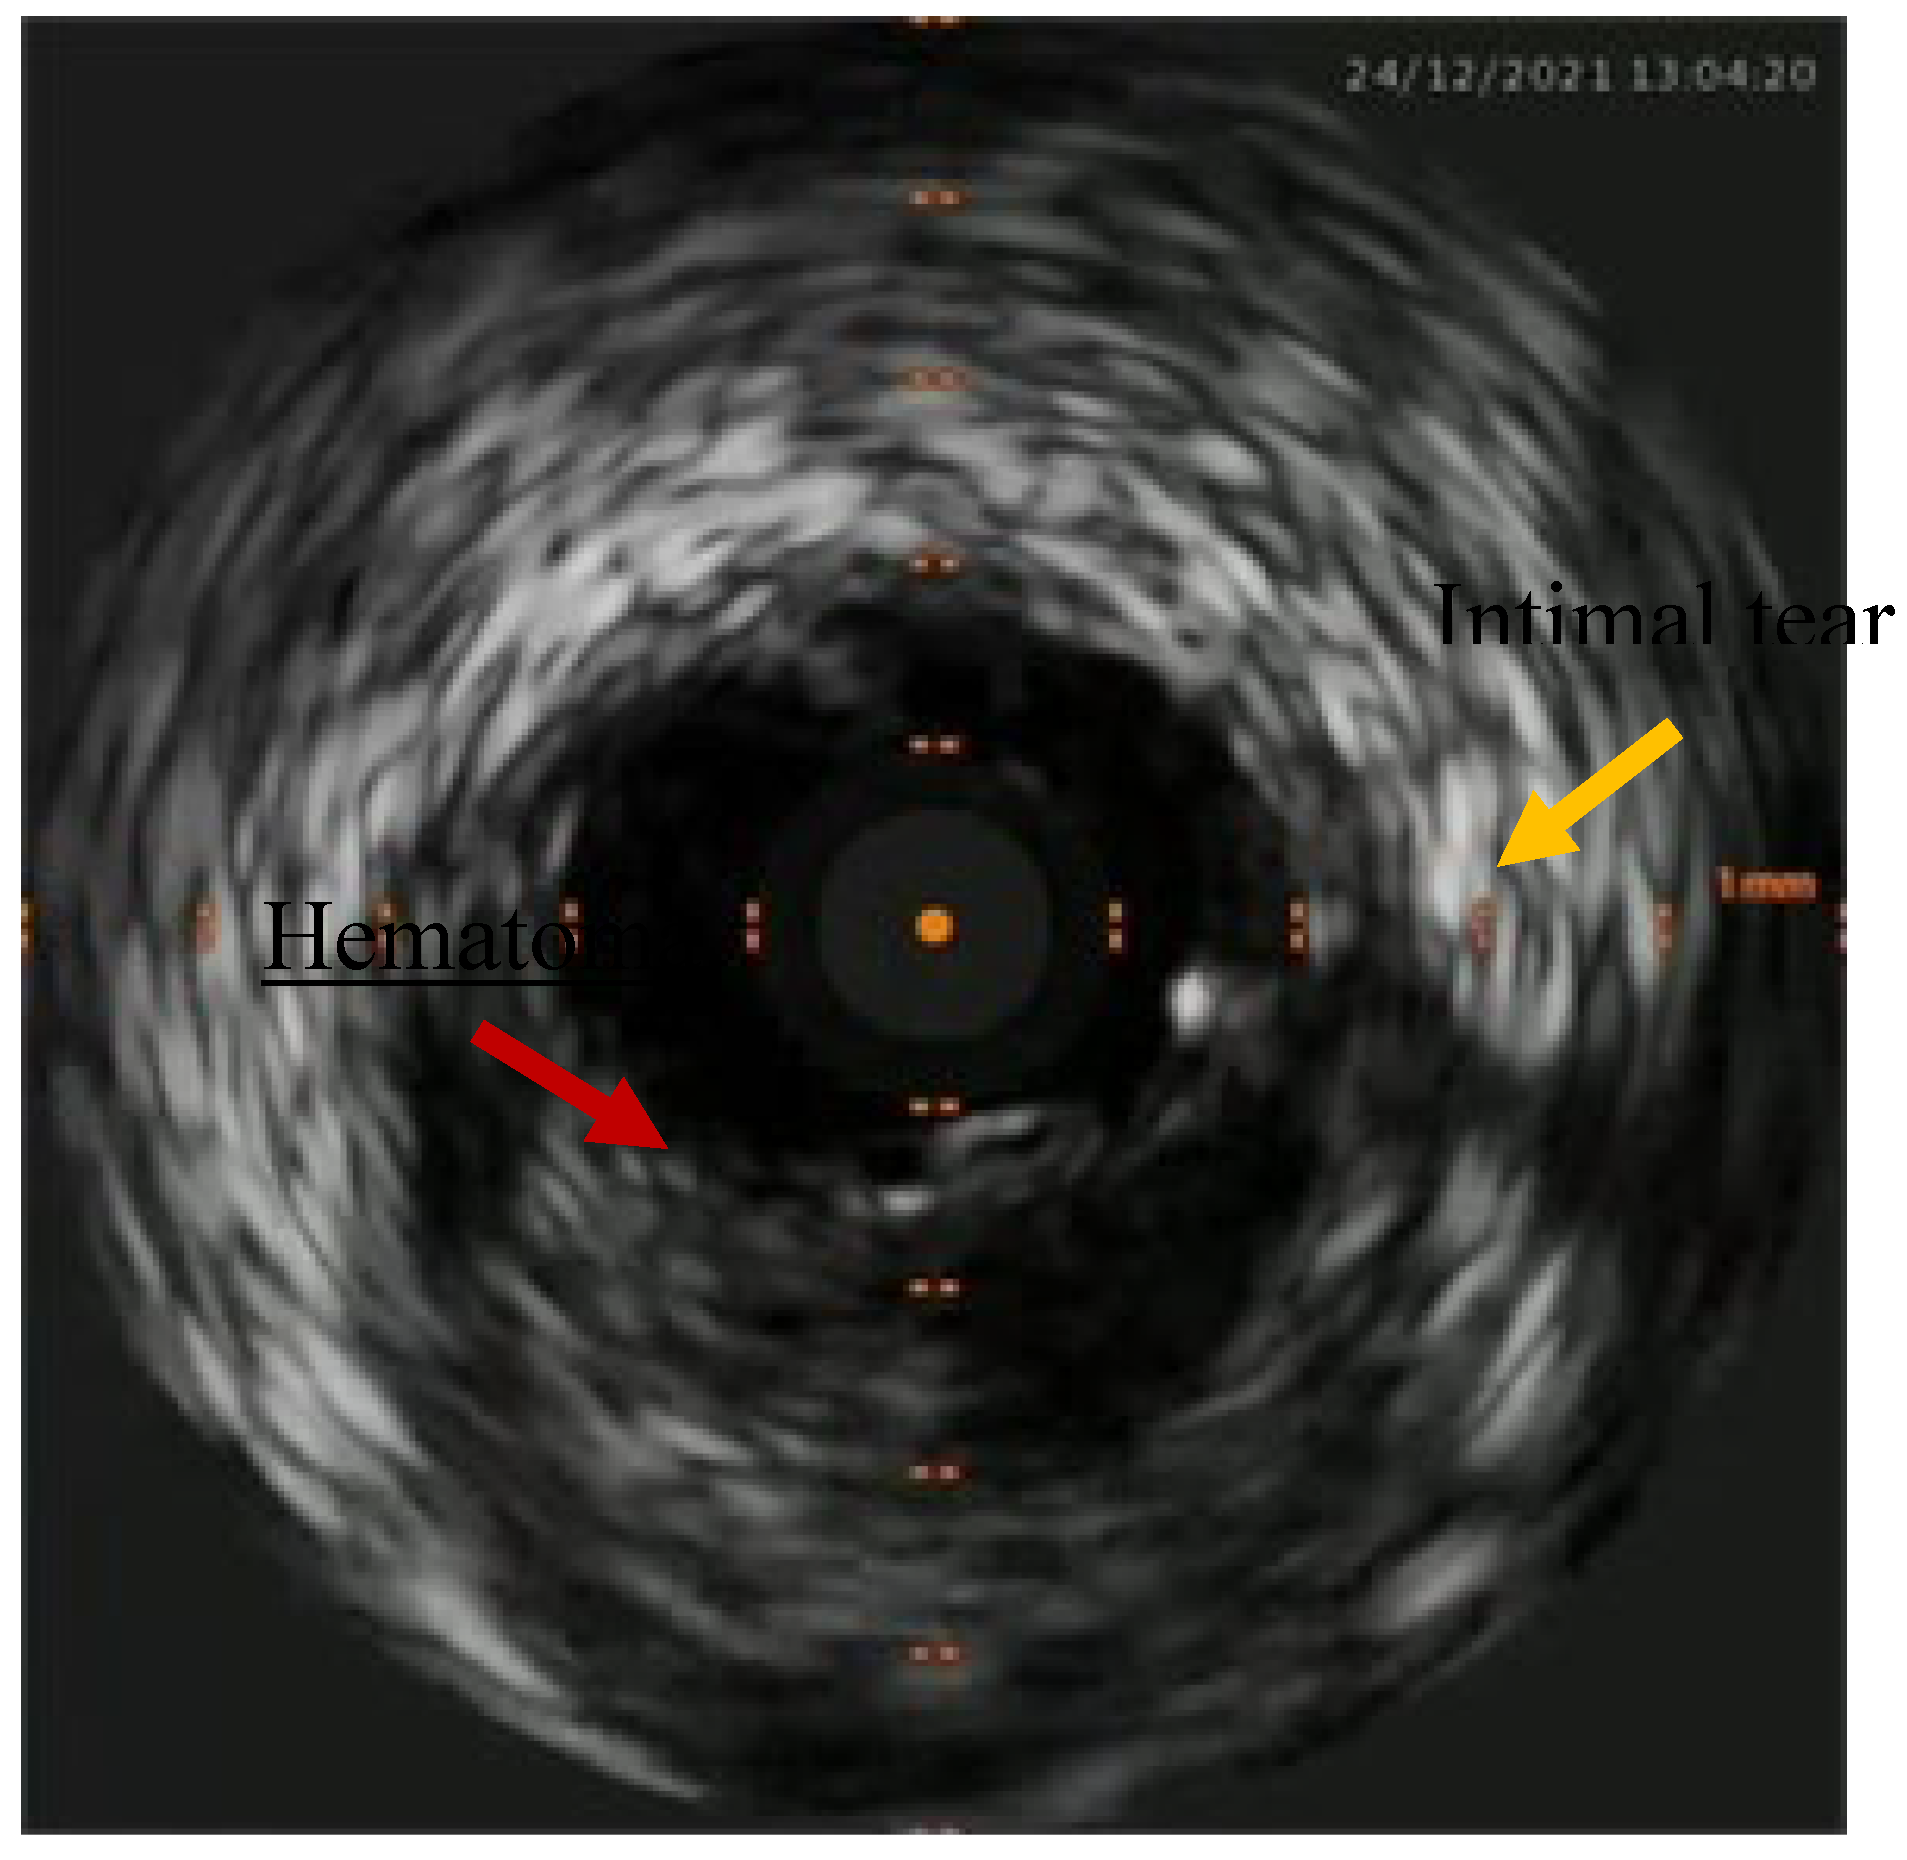

Figure 3. Intimal tear in the left main with hematoma.

Percutaneous coronary intervention was therefore considered appropriate and a purposely undersized EBU 3.0 6F was selected. Regarding mechanical circulatory support only intra-aortic balloon pump was available. After rapid consultation, considering the insertion of the device, a decision was made to not proceed given the potential lengthening of the procedure, the need for femoral access and the issue of scanning the fetus with the XR detector. A safety wire, Terumo Runthrough floppy, was immediately placed on the patent left circumflex artery whilst after failing wiring on the left anterior descending with a Balance Middleweight wire a Sion wire was advanced up to the apical LAD. An IVUS run confirmed distal true lumen wire position showing a short subintimal track without compromise of any major side branch (Figure 2, Figure 3, Figure 4 and Figure 5).